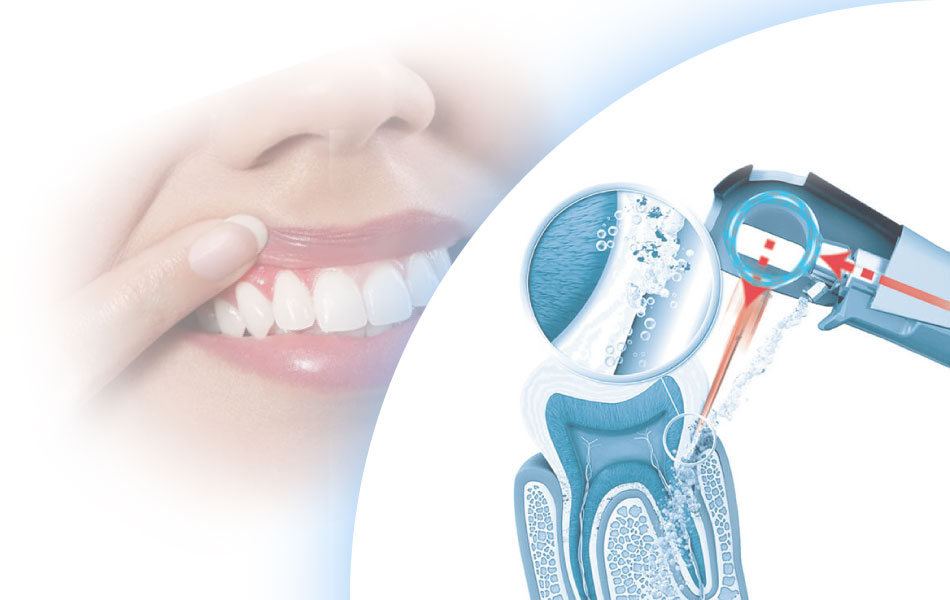

Консервативная терапия – щадящий вариант, который может осуществляться двумя путями. Сегодня стоматологи предлагают пациентам:

- механическую чистку специальными инструментами;

- атравматичную чистку ультразвуком (на аппарате «Вектор») или лазером.

Оба способа позволяют снять как мягкий, так и твердый зубной налет. В результате устраняется благоприятная для размножения микробов среда. Зубы становятся белыми, а десны постепенно перестают кровоточить и отекать.

Хирургическое лечение десен, или открытая чистка, – метод, актуальный при глубоких повреждениях. В ходе манипуляции под визуальным контролем механически и с применением антисептических растворов очищается пародонтальный карман и поверхность корня.